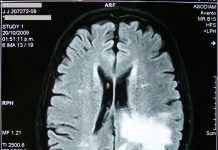

Flu-like virus being used to fight incurable brain cancer

UK scientists are optimistic that using a common flu-like virus is the next best treatment to help tackle incurable brain cancer.

According to recent studies,...